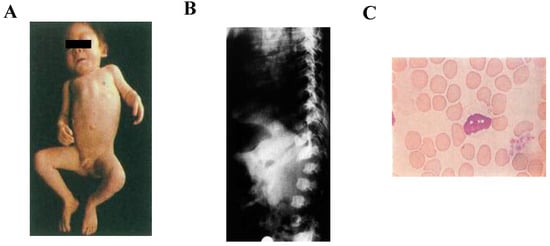

Mucolipidoses (MLs) are classified as a lysosomal storage diseases (LSDs) because of their involvement in increased storage materials in the lysosomes. Around 50 LSDs have been identified so far, and the incidence is approximately 1 in every 7000 births [1]. Patients with MLs are born with a genetic defect in which their bodies either do not produce enough enzymes or, in some instances, produce ineffective forms of enzymes, resulting in the accumulation of storage materials in the cells of various tissues in the body and successive damage of organs [2]. In patients with MLs, the molecules accumulate in the brain, visceral organs, and muscle tissue as well as in the bone, causing mental retardation, skeletal deformities, and poor function of vital organs such as the liver, spleen, heart, and lungs. There are four types of ML which are classified according to the enzyme(s) that is deficient or mutated: sialidosis (ML I), ML type II, initially called “inclusion cell disease or I-cell disease [3]”, now known as ML II alpha/beta (α/β) [4], ML type III (previously known as pseudo-Hurler polydystrophy, [5]), later as ML IIIA and ML IIIC, and now known as ML III α/β and ML III gamma (γ), respectively [4], and ML IV. In this review, we will focus on ML II α/β and ML III α/β in more detail and will refer them as ML II and ML III, respectively. Sialidosis is caused by the deficiency of alpha-N-acetyl neuraminidase due to mutations in the neuraminidase 1 gene (NEU1) resulting in the accumulation of sialylated glycoconjugates [6]. ML II is a severe form of ML in which children usually have an enlargement of certain organs, such as the liver or spleen, and sometimes even the heart. Affected children often fail to grow and develop in the first months of life. Delays in the development of their motor skills are usually more pronounced than delays in their cognitive skills. Children with ML II eventually develop a corneal clouding and, because of their lack of growth, develop short-trunk dwarfism. ML II patients exhibit clinical phenotypes at the prenatal or neonatal stage. Postnatal growth is reduced significantly within 1–2 years. ML II patients have several severe skeletal abnormalities, including craniosynostosis, osteopenia, neonatal hyperparathyroidism, rickets, thoracic deformity, kyphosis, deformed long tubular bones, hip dysplasia, clubfeet, and contractures in all large joints. Skeletal radiographs reveal signs of dysostosis multiplex that includes metacarpal pointing, bullet-shaped phalanx, oar shaped ribs, and iliac flaring. The progressive deformity of vertebral bodies presents anterior beaking or wedging and later results in kyphoscoliosis. Prenatal manifestations can include bone dysplasia with shortened and curved bones and/or bone fractures [7,8,9,10,11,12,13]. Figure 1A represents a full-body image of a 13-month-old patient with I-cell disease. The patient has a unique clinical appearance. Figure 1B shows the vertebral side image of a 9-month-old boy with I-cell disease with characteristic features of skeletal dysplasia. Peripheral blood lymphocytes of I-cell disease show abnormal vacuoles (Figure 1C).

Figure 1.

Clinical feature of I-cell disease (kindly provided by Dr. Tadao Orii). We have signed the inform consent (A). A full-body image of the patient with I-Cell disease (a 13-month-old boy). The patient has a distinct coarse face, short neck, umbilical hernia, thick skin, and rigidity of joints. (B). The vertebral side image of a patient with I-cell disease (a 9-month-old boy). Anteroposterior diameter of the vertebral body and ossification of the anterior upper border of the lumbar vertebral body are reduced. Dysfunction is observed and hump-back of the vertebral L2 body. (C). Peripheral blood lymphocytes (at 40× magnification) of I-cell disease (mucolipidosis II) (May-Giemsa staining). The cytoplasm is filled with numerous vacuoles.